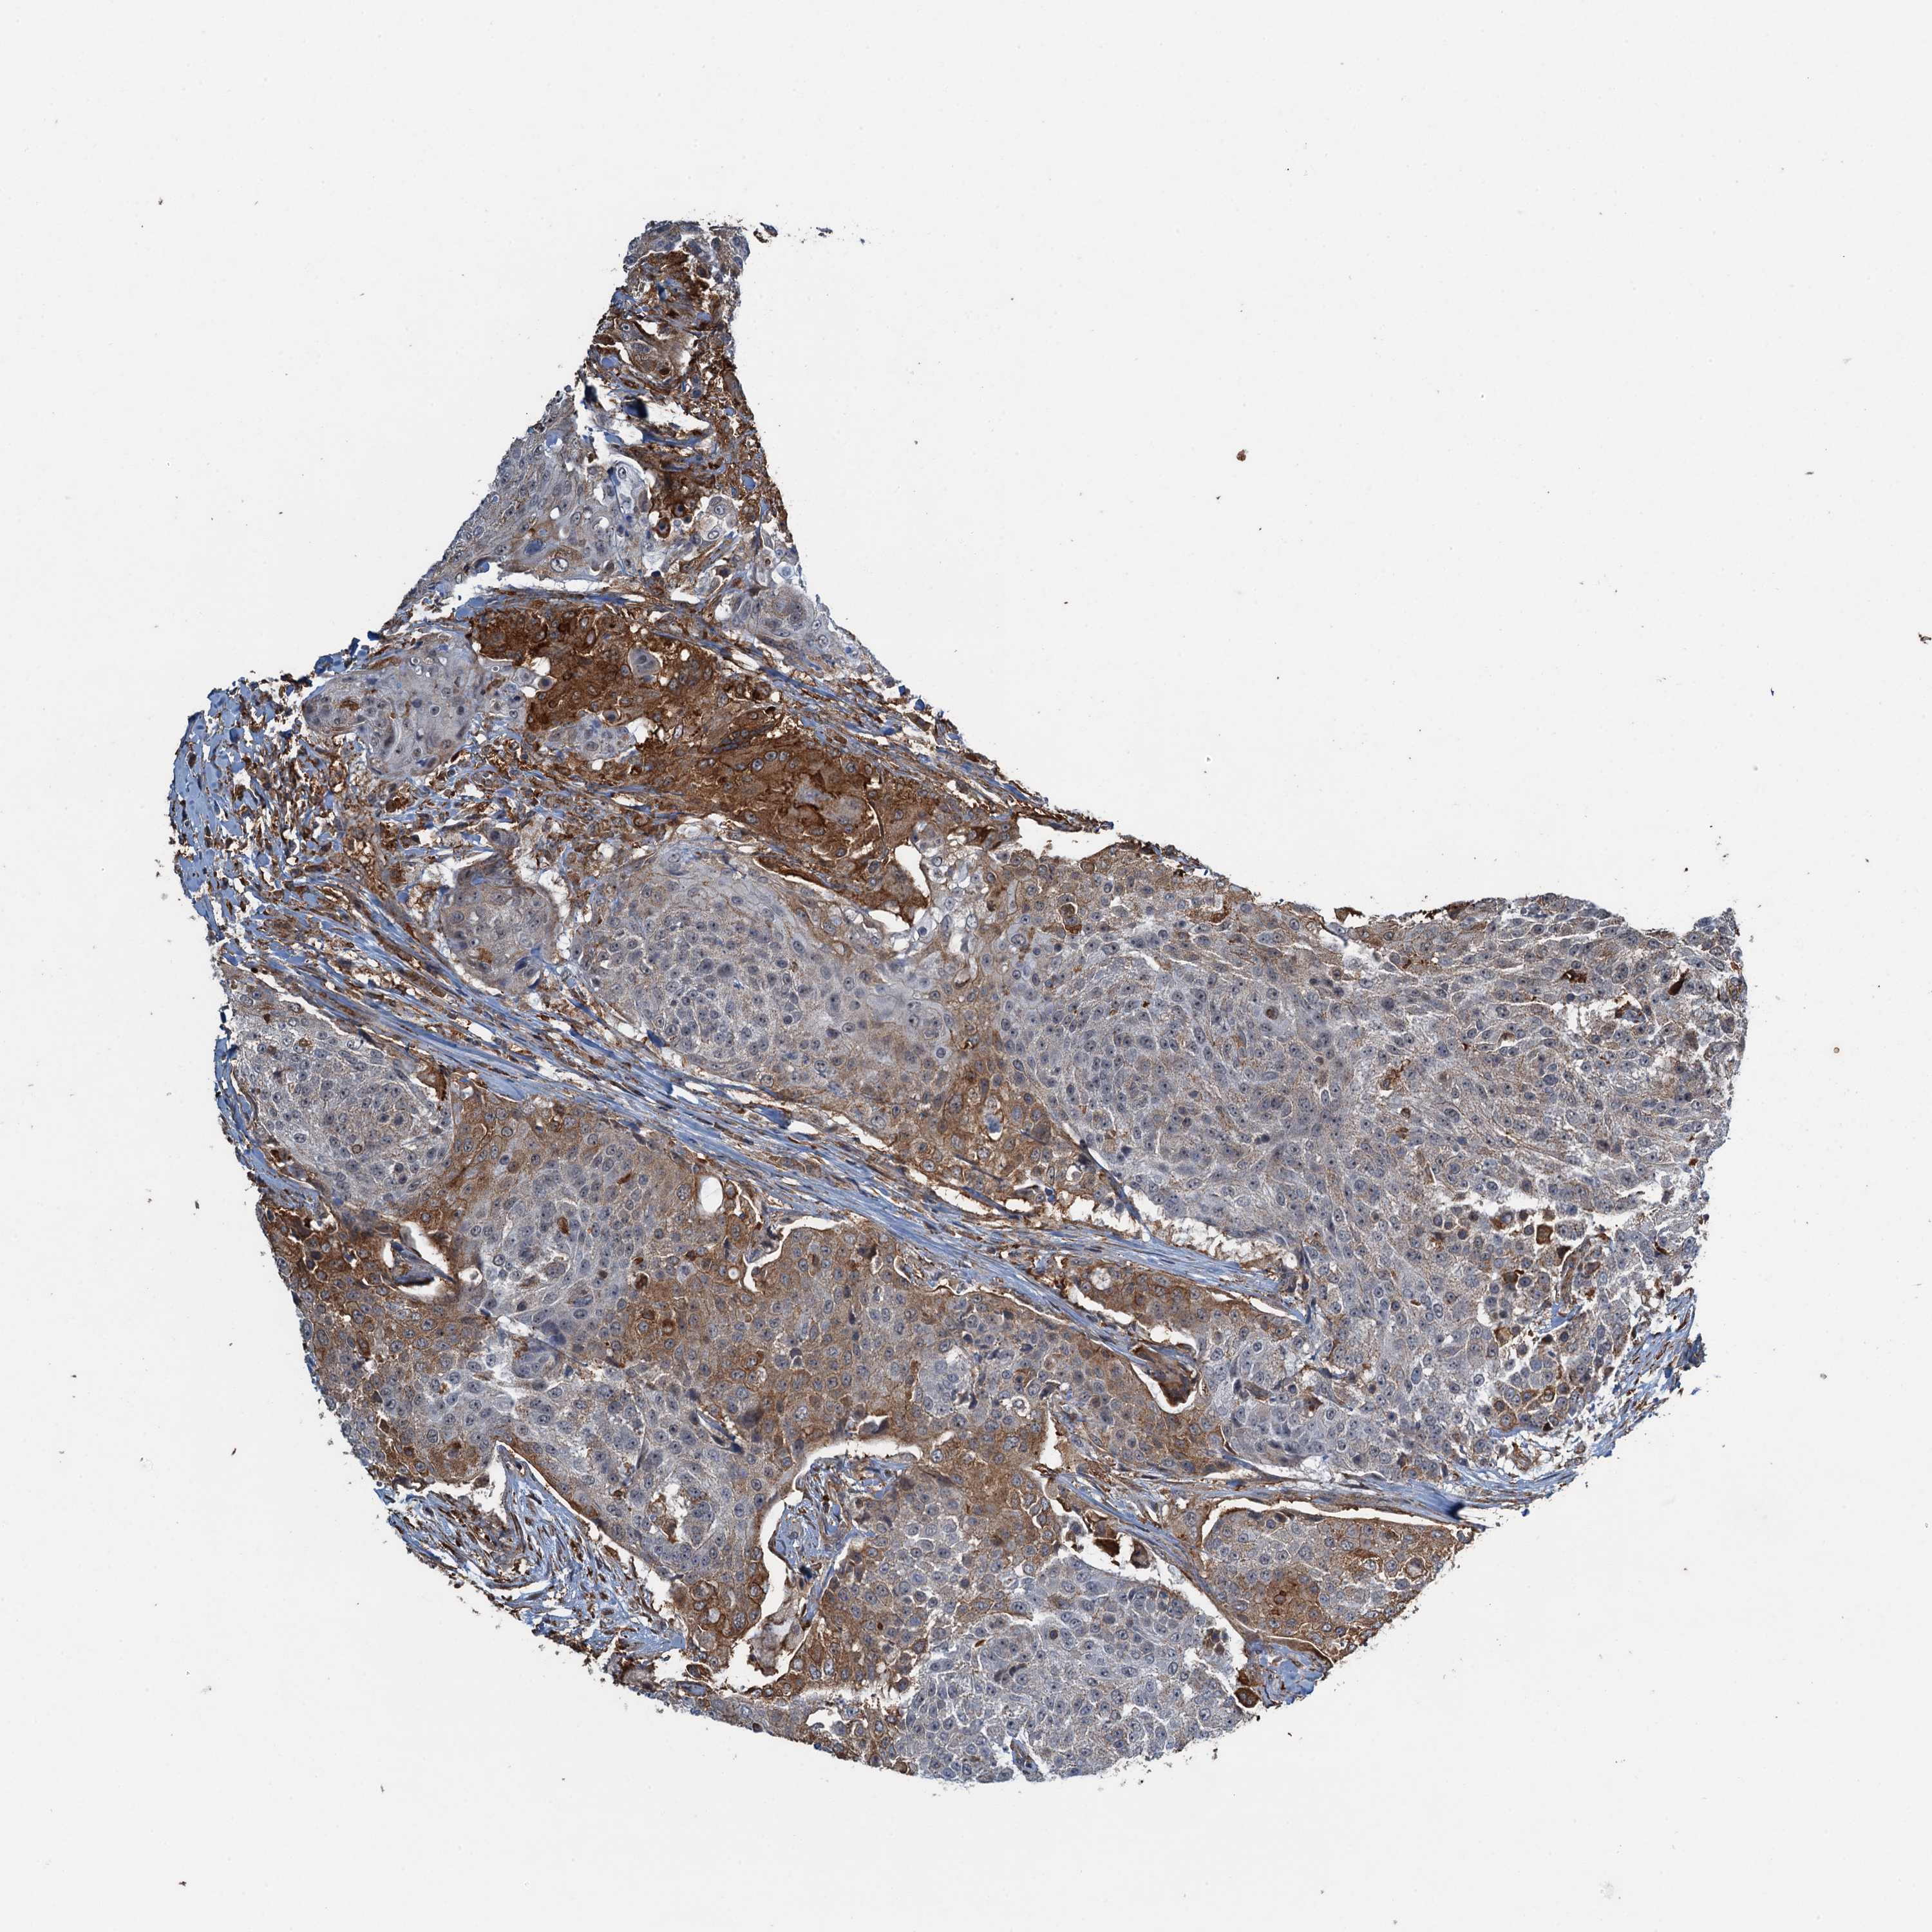

UROTHELIAL CANCER - Protein expressioni

A mouse-over function shows sample information and annotation data. Click on an image to view it in a full screen mode. Samples can be filtered based on level of antibody staining by selecting one or several of the following categories: high, medium, low and not detected. The assay and annotation is described here.

Note that samples used for immunohistochemistry by the Human Protein Atlas do not correspond to samples in the TCGA dataset.

Antibody stainingi

Antibody staining in the annotated cell types in the current human tissue is reported as not detected, low, medium, or high, based on conventional immunohistochemistry profiling in selected tissues. This score is based on the combination of the staining intensity and fraction of stained cells.

Each image is clickable and will lead to virtual microscopy that enables deeper exploration of all samples and also displays staining intensity scores, fraction scores and subcellular localization as well as patient and tissue information for each sample.

Antibody HPA039690

Antibody HPA040231

Urothelial carcinoma, High grade

Urothelial carcinoma, Low grade